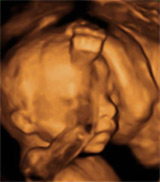

El feto presenta una cantidad de grasas en la semana 20 de gestación, que coincide con la mitad del embarazo, de tan sólo un 1 por ciento de su peso.

Este porcentaje va aumentando progresivamente hasta convertirse en un 7 a 8 por ciento en las 34 semanas de embarazo, y hasta un 16 por ciento en el feto en el momento del nacimiento. Por ello, es en el segundo y tercer trimestre cuando el metabolismo fetal contribuirá a la formación de estas grasas.